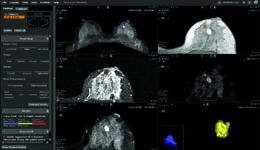

Editor's Note: This article is an introduction to the breast MRI comparison chart that ran in the July/August 2010 issue ...

June 24, 2010 ? A U.S. breast MRI system manufacturer announced its first installation in China this week. The Aurora ...

Unlike whole-body MRI systems, which require after-market modifications to image the breast, the Aurora 1.5T Dedicated ...